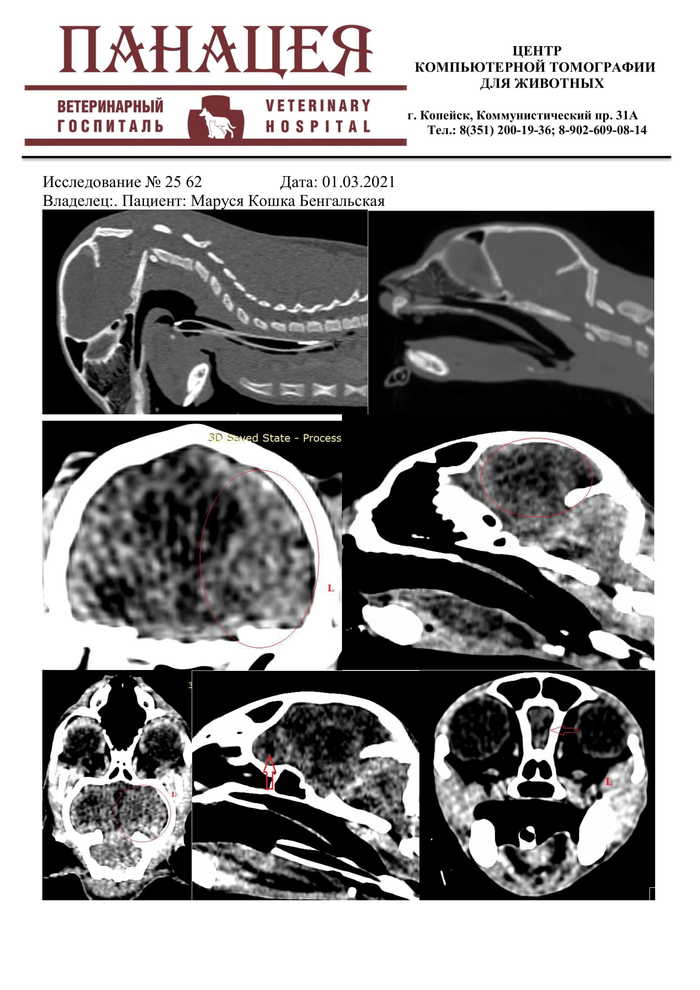

Результаты КТ (г.Копейск). Если кто поймет, пишите, А так ЧМТ. С позвоночником все нормально, вправили совместными усилиями с нашим Вартовским доктором посредством массажа и умелых рук доктора.